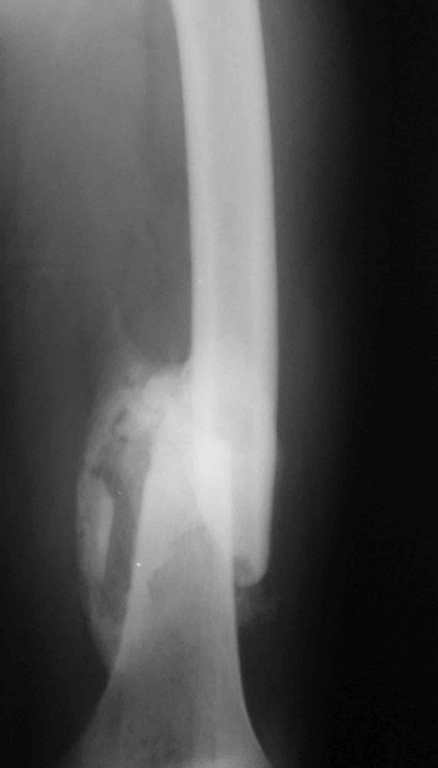

Re: 32- летний пациент с переломами обоих бедер после неудачного оперативного и консервативного лечения.

Иллюстрации к сообщению

Уважаемый Антон.Исходя из Вашего материального положения!! и наличия хорошего, грубого омозоления, равности длины конечностей и судя по снимкам не очень выраженной антекурвации, но выраженной контрактуры коленных суставов: чтоб не упустить время разработки суставов и активизировать больного, необходимо справа удалить стержень, рассверлить канал и произвести ЗИМО более толстым неблокир. стержнем т.к. на этом уровне можно получить устойчивый остеосинтез, после чего активизировать и дозированная, упорная ЛФК, а дальше после восстановления функции ,время покажеть.

Cyдя по представленным рентгенограммам оба бедра консолидированы. Необходима активная разработка движений в коленных суставах. Хотелось бы увидеть фотоснимки больного ( нижних конечностей спереди и сбоку). Если стержень мешает разработке движений то его надо удалить.

О происхождении такого запущенного случая- мой коллега работает экспертом ВТЭК и тянет в отделении и не такие казусы. Сегодня была сделана операция удален стержень из бедра и установлен стержневой аппарат из 2 опор, слева подвижности не наблюдалось, продолжается ЛФК. При необходимости позднее будет выполнена надмыщелковая корригирующая остеотомия. Спасибо всем за советы.